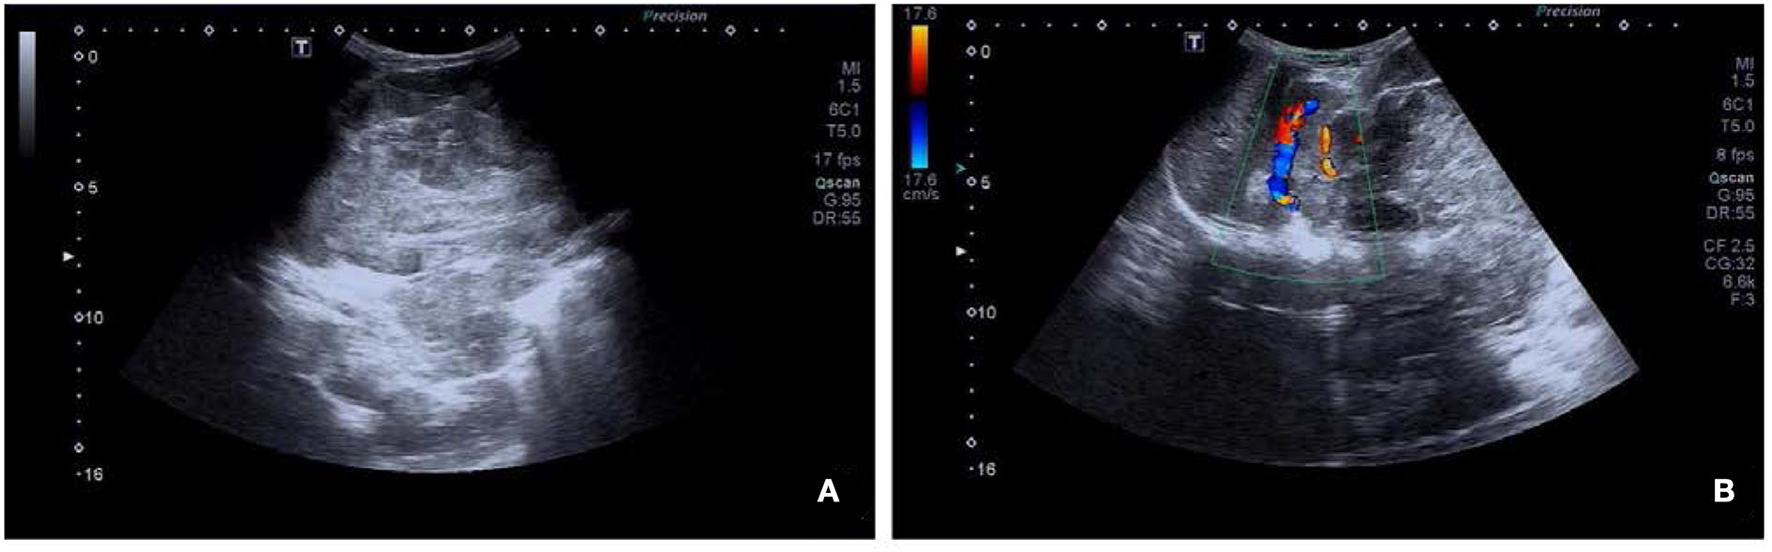

A 3-year-old female was accidentally found with a large left upper abdominal mass for a day. By physical examination, a smooth, hard, painless, and firm mass of about 14 cm in the left upper abdomen was found. Laboratory test showed increased fibrinogen of 4.08 g/L (reference range 2–4 g/L), neuron-specific enolase (NSE) of 79.90 ng/mL (reference range 15.6–17 ng/mL), and tumor abnormal protein (TAP) of 135.60 (reference range 1–121). An ultrasound showed a solid mass of about 13.8 × 10.4 cm in the left upper abdomen, with an unclear boundary with the left kidney. Blood flow signal could be observed using the color doppler flow imaging (CDFI) technique (Figure 1).

Figure 1

Ultrasound images of retroperitoneal alveolar rhabdomyosarcoma (ARMS). (A) A heterogeneous hypoechoic area of about 13.8 × 10.4 cm in the left upper abdomen, with an unclear boundary with the left kidney. (B) Blood flow signal observed using color doppler flow imaging (CDFI).

Medical imaging provides noninvasive methods which are essential for the evaluation of patients with ARMS. The sonographic feature of ARMS is substantive hypoechoic or complex-echoic mass. CDFI shows rich and disorderly color blood flow signals within the mass. It often appears as an equal or a slightly low-density mass in plain CT, with unclear borders. The tumors usually grow rapidly, and necrosis, as well as cystic degeneration, can be seen in the lesions as a result of the insufficient blood supply. Enhanced CT scan shows heterogeneous enhancement and sometimes rim-like enhancement. Areas without enhancement are tissues with necrosis and cystic degeneration. Hemorrhage and calcification occur rarely, but mottling calcification was observed in this case. Moreover, CT can detect adjacent bone involvement but ARMS frequently destroy the bone. PET/CT reveals increased glucose metabolism of ARMS. As an advanced technology, PET/CT could provide more information about the lesions than conventional imaging detection methods. 18F-FDG PET/CT imaging is useful for initial assessment, monitoring treatment response, and detection of recurrences with better accuracy for identifying primary sites, lymphatic involvement, and distant metastases (22, 23). Local lymph node metastasis has been considered a strong prognostic factor, calling for an emphasis on desirable detection modalities of lymphatic involvement (24). Compared with conventional imaging techniques, such as ultrasound, CT, and magnetic resonance imaging (MRI), PET/CT performs better in detecting lymph nodal metastasis with higher sensitivity and specificity (25). 18F-FDG PET/CT can estimate the function and nature of nodes through the level of glucose metabolism in tissues and can help with accurate localization of the involved lymph nodes. In a prospective study by Völker et al. (25), the detection of involved lymph nodes using 18F-FDG PET/CT reached a sensitivity of 93%, whereas conventional imaging modalities were only 36%. Ricard et al. (26) reported that 18F-FDG PET/CT found 19 involved lymph nodes in 4 patients vs. 12 nodes by MRI and CT, and therefore, the results of PET/CT led to alteration of the lymph node staging and treatment strategies in some patients. Our case also observed similar advantages of PET/CT for discovering retroperitoneal lymphatic metastases, whereas negative in ultrasound and CT tests. The more accurate staging of regional lymph node involvement will benefit risk stratification and treatment decisions in patients with RMS. PET/CT also shows some potential superiorities in finding tumor invasion into the spinal canal. When evaluating the spinal canal involvement, all background tissues, including paraspinal musculature, vertebrae, spinal cord, nerve roots, and CSF, demonstrate relatively low metabolic activity using 18F-FDG PET/CT, thus making it possible for differentiation between normal tissues and lesions (27, 28). PET/CT allows for the identification of soft-tissue involvement such as neural foramen invasion and epidural extension of tumor in malignant involvement of the spine (29). However, PET/CT is inferior to MRI when used to detect spinal cord involvement. In recent years, the integrated PET and MR (PET/MR) imaging modality has been rapidly developed with the combined superiorities of quantification of radioactive tracer metabolism provided by PET and outstanding soft tissue contrast by MR (30). The value of PET/MR in clinical applications remains to be established, and we hope this innovative technology will provide more accurate diagnosis and ultimately improve patient prognosis. In addition, a study illustrated that metabolic parameters obtained from baseline PET/CT were potential to select patients sensitive to treatment (31). Features of patients including unfavorable sites of the primary tumor, older patient age at initial presentation, the alveolar subtype, and regional lymph node involvement are considered to be poor prognostic factors for RMS (5, 32). Unfavorable sites include the prostate and bladder, cranial parameningeal sites, extremities, trunk, retroperitoneum, and other sites (13). Moreover, 18F-FDG PET/CT may be an added prognostic predictor in RMS. High SUVmax value is more prevalent among patients with less favorable features including unfavorable primary sites, alveolar pathology, and high-risk group (33). A study found that during diagnosis, patients with SUVmax of <9 had an improved 3-year progression-free survival (62% of patients with SUVmax of <9 vs. 39% of patients with SUVmax of ≥9, p = 0.02) (34). In our case study, the SUVmax of 7.0 might be associated with the patient's favorable prognosis.